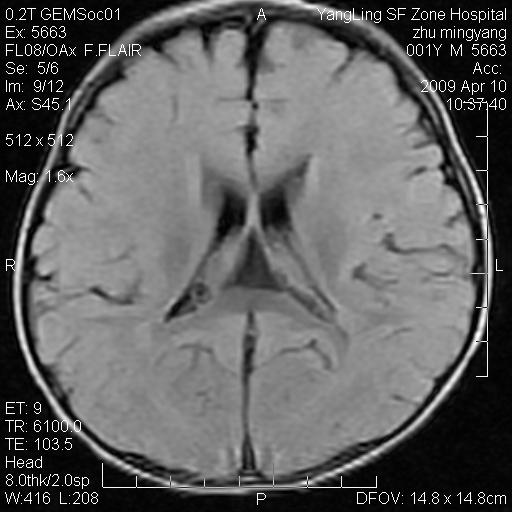

患者:1岁半,两天前外伤收住我院,ct检查小脑占位

考虑星形细胞瘤,建议增强

髓母细胞瘤或血管母细胞瘤,增强后可以鉴别;影像资料见 <。鱼博浪老师的《中枢神经系统ct与mr鉴别诊断》 小脑部肿瘤章节。

髓母细胞瘤或血管母细胞瘤!支持!

支持考虑髓母细胞瘤

考虑----髓母细胞瘤可能性大

考虑髓母细胞瘤或室管膜瘤。

支持髓母细胞瘤。

考虑髓母细胞瘤。

考虑髓母细胞瘤或星形细胞瘤

考虑髓母细胞瘤.

考虑髓母细胞瘤可能性大。

小脑肿瘤.考虑髓母细胞瘤可能.

就病灶部位及临床资料首先考虑髓母.